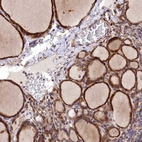

Immunohistochemistry analysis in human thyroid gland and pancreas tissues using Anti-MRPS11 antibody. Corresponding MRPS11 RNA-seq data are presented for the same tissues.